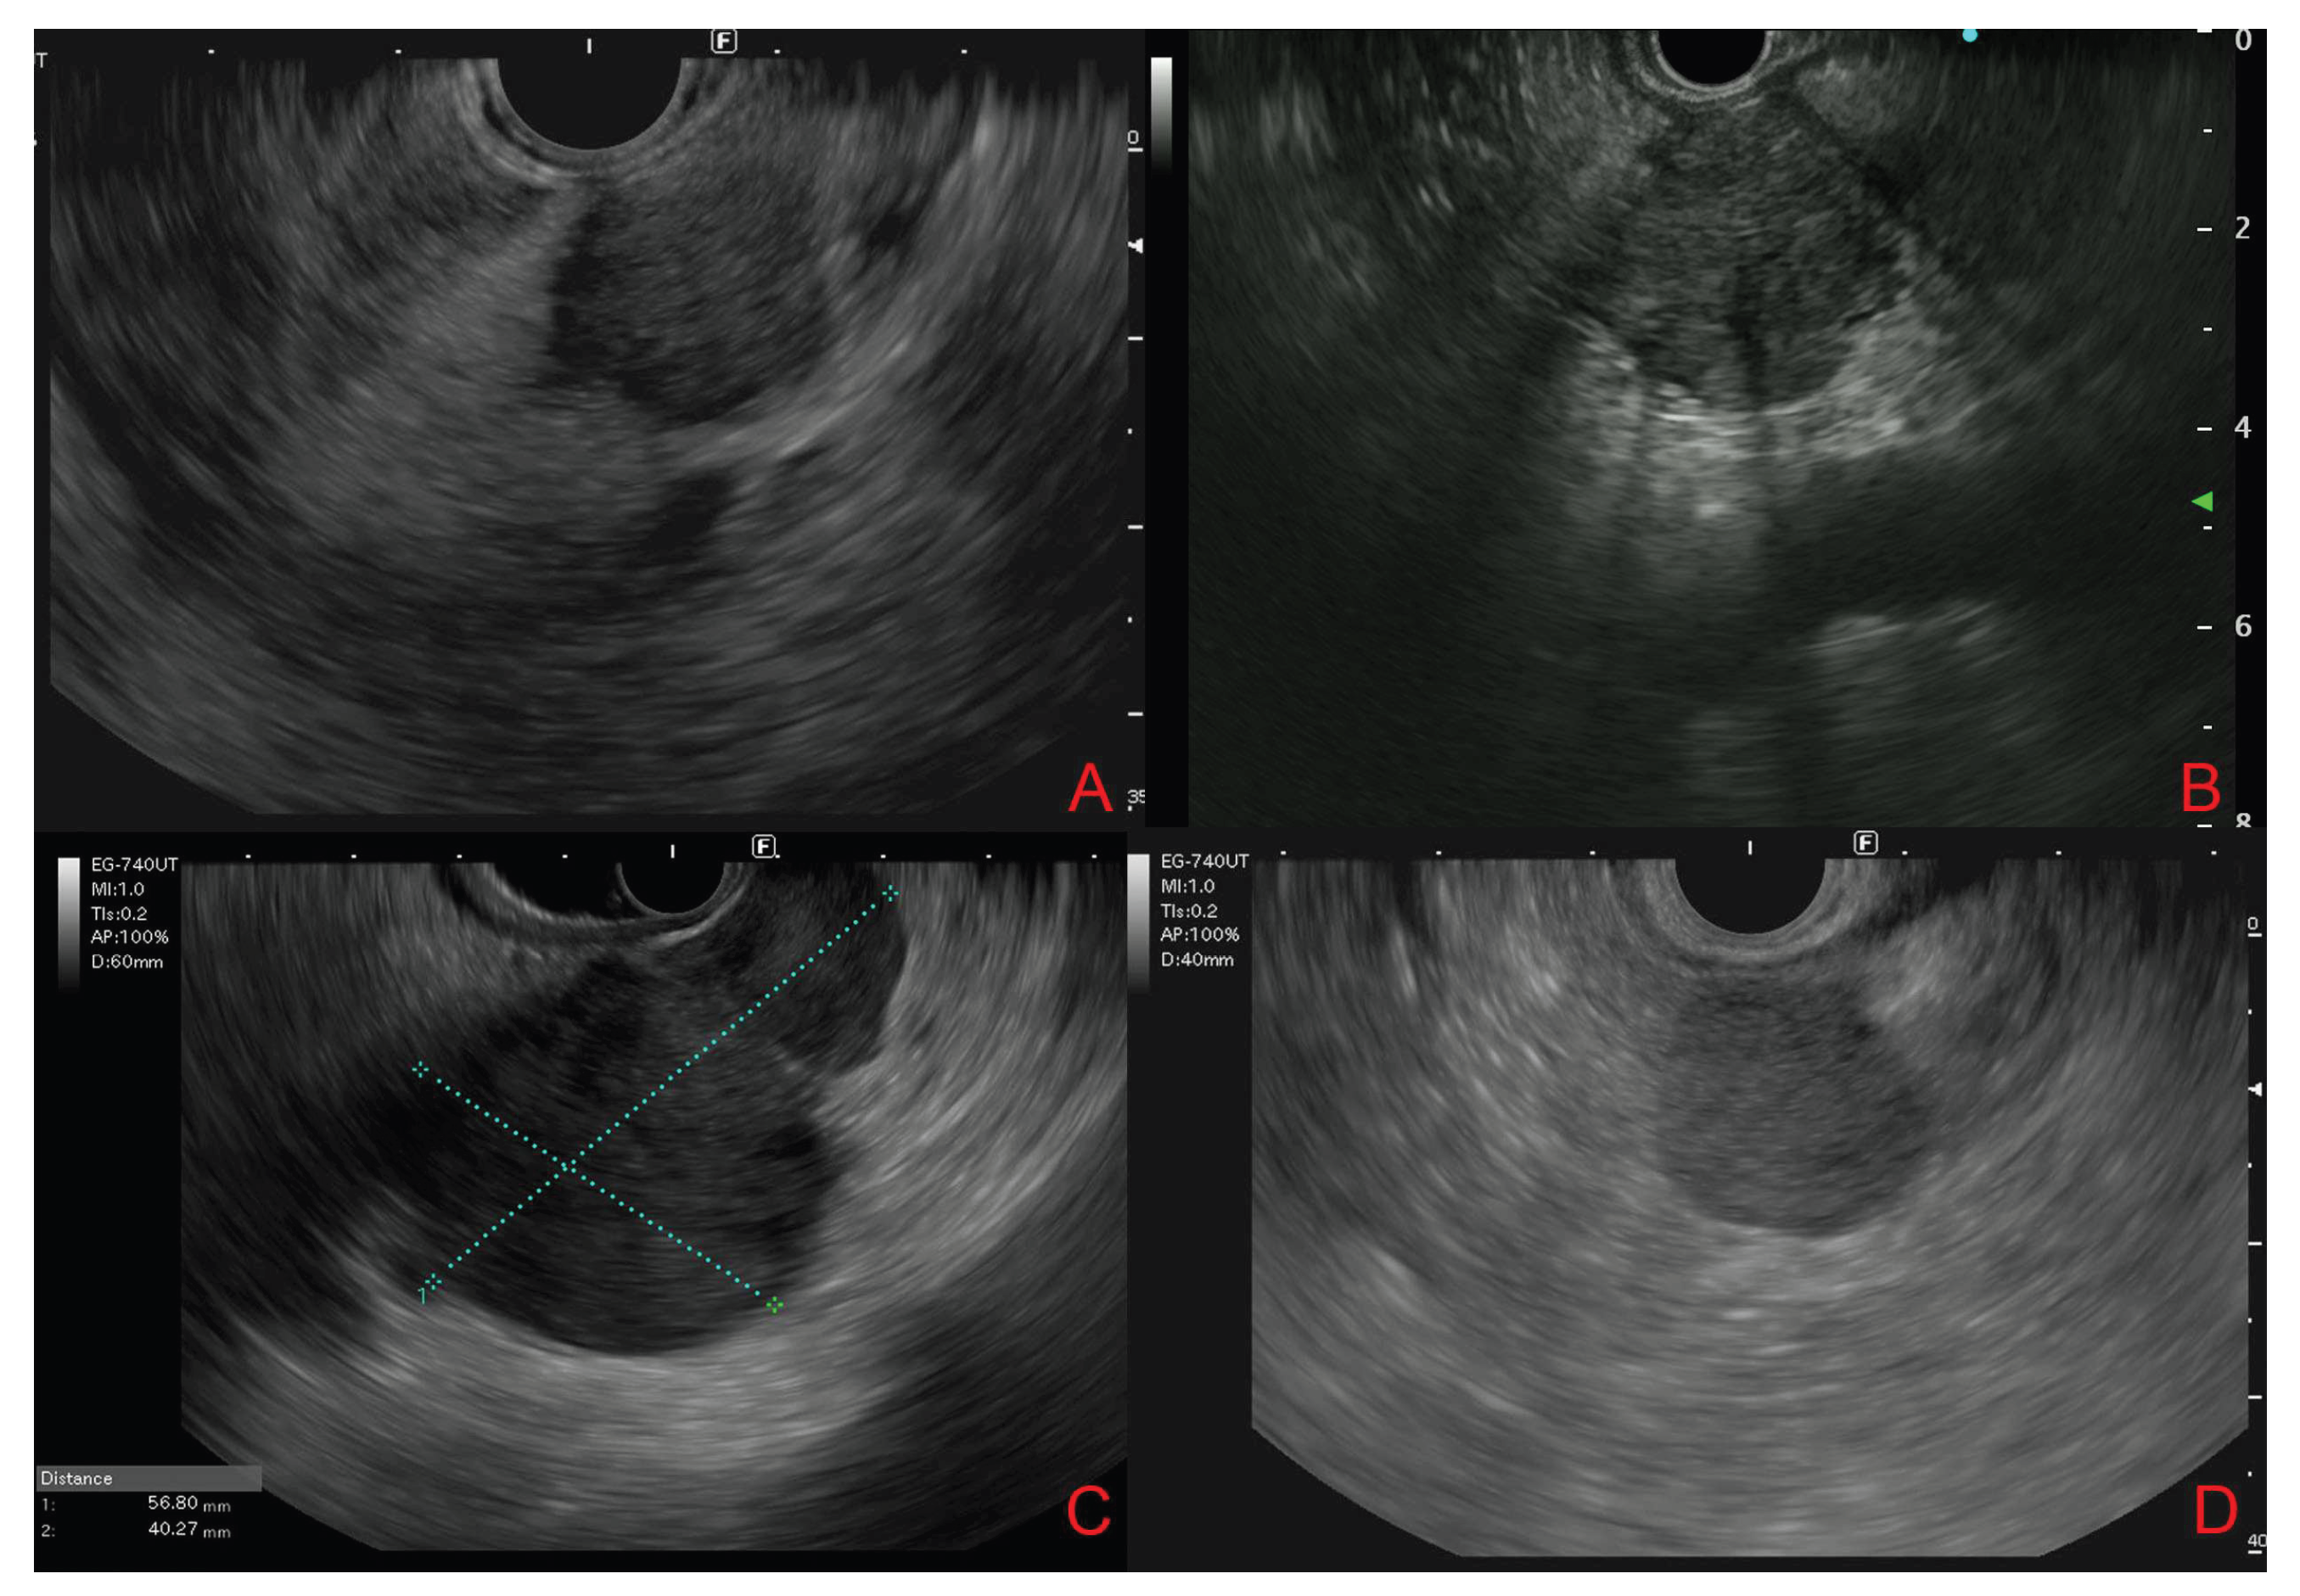

3.4. Endoscopic Ultrasound Morphological Features

3.5. Contrast-Enhanced Endoscopic Ultrasound Features